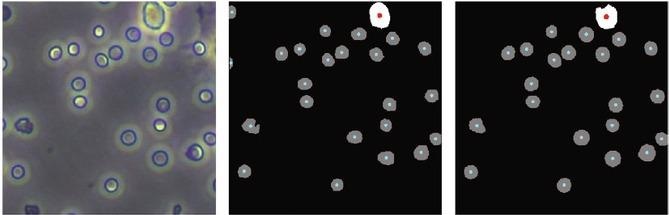

Results of cell counts compared to predicted count results showed that the newly developed training method allows machine learning to more accurately count blood cells. Image Credit: Cyborg and Bionic Systems

Much recent research on alternatives has focused on the use of computer algorithms to do “segmentation” on images of blood obtained by a high-definition camera linked to a microscope to increase accuracy, keep things simple, and minimize costs. Segmentation entails algorithms that label what emerges in a photo pixel by pixel, in this example, which sections of the image are cells and which are not basically, counting the number of cells in an image.

These single-cell photos are automatically “preprocessed” by traditional algorithms that decrease noise, improve image clarity, and recognize the contours of objects in the image. They then do adaptive picture segmentation. This algorithm analyzes the different levels of grey in a black and white image, and if a portion of the image lies beyond a specified grey threshold, it is segmented as a separate item.

The researchers employed a typical cell analyzer on the identical mouse blood samples to perform an unbiased cell count against which they could contrast their new training system. They discovered that their training strategy segmented multiple-cell-type images with an efficiency of 94.85%, which is the same as training with manually annotated multiple-cell-type images.